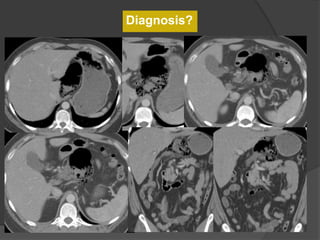

Case 1: 24 F with left sided pleuritic chest pain

CT 5 years ago

Diagnosis?

CT 5 years agoCurrent CT

Case 1 Diagnosis: Infarcted splenule

Infarcted splenule

 Accessory spleen (splenule ) : failure of fusion of the splenic

anlage, seen in up to 30% of autopsies

 Occur on vascular pedicles and thus at risk for torsion

 Differentiate from polysplenia and splenosis. Identify an intact

spleen, no other splenic foci and normal situs

 Recognize this entity as a cause of abdominal pain that can be

managed non-surgically

Case 14: 24 F with left sided pleuritic chest pain

Case 14 Diagnosis: Infarcted splenule

Emerg Radiol (2007) 14:123-125